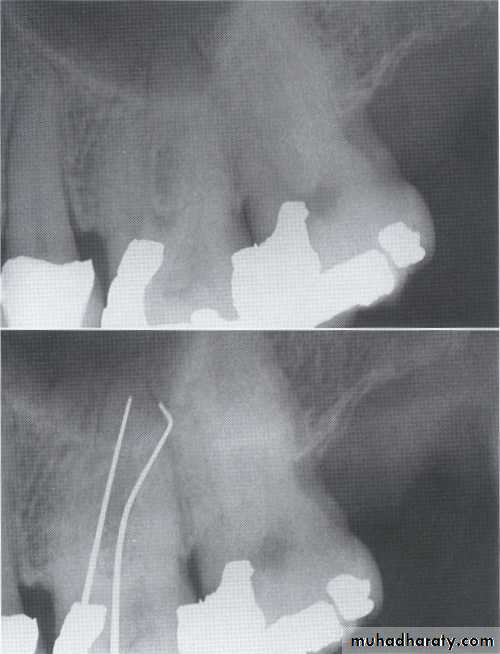

Often infrabony defects are difficult or impossible to recognize on a radiograph because one or both of the cortical bony plates remain superimposed with the defect.

Clinical and surgical inspections are the best means of determining the number of remaining

bony walls.

Visualization of the depth of pockets

may be aided by inserting a gutta-percha

point.